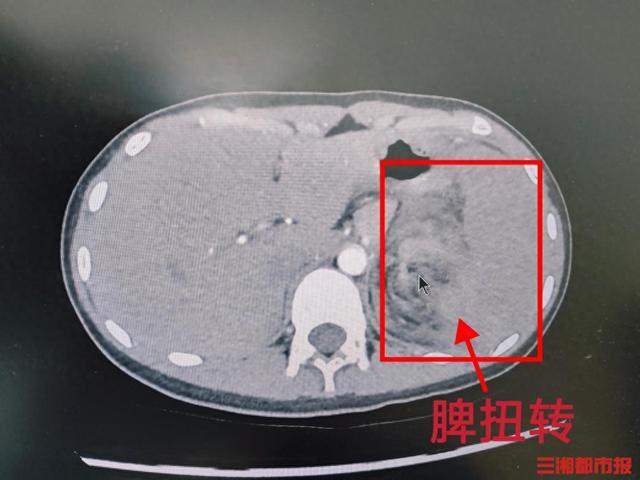

橙橙转诊到湖南省儿童医院后,接诊医师对她进行了全面检查,结合影像学结果,诊断为脾扭转和脾梗死。这种急腹症起病隐匿、症状不典型,容易与普通腹痛或肠胃炎混淆。病情发展迅速,一旦脾脏缺血坏死或破裂出血,可能引发休克甚至危及生命。

医院立即启动急诊绿色通道,普外一科主任尹强带领的手术团队迅速展开救治。术中发现橙橙的脾蒂逆时针扭转720度,复位后脾脏无任何血运改善迹象,已完全梗死。凭借丰富的经验和娴熟的技术,团队顺利完成了脾脏切除手术。